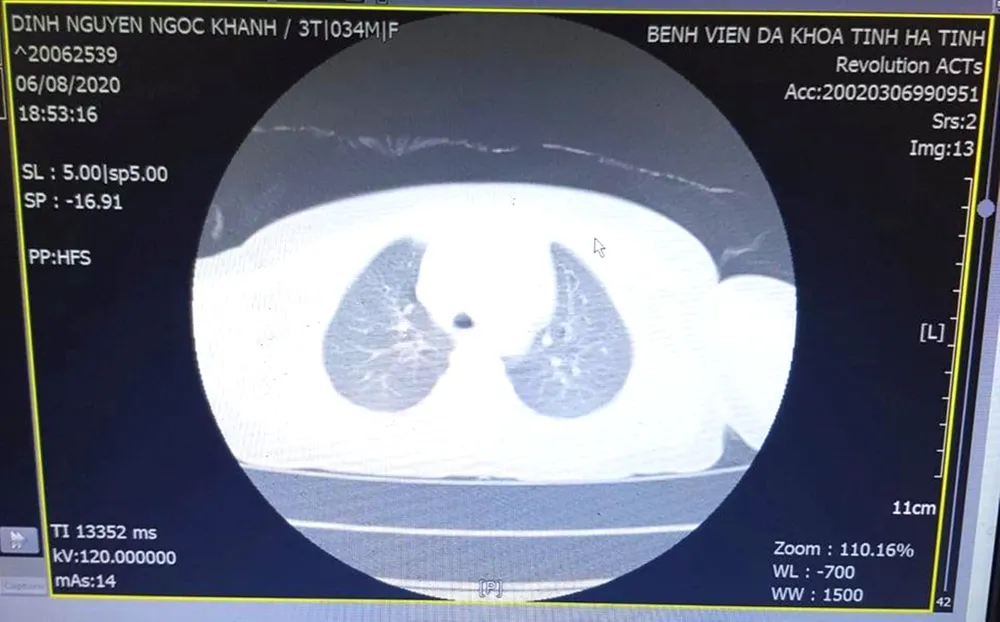

Hình ảnh dị vật thông qua chụp CT- Scanner của bệnh nhi K.

Đến tối ngày 6-8, do các triệu chứng không thuyên giảm, vẫn xuất hiện tình trạng khó thở, ho nhiều, gia đình đưa cháu K. đến điều trị tại Khoa Tai - Mũi - Họng, Bệnh viện Đa khoa tỉnh Hà Tĩnh. Tại đây, bệnh nhi K. được các bác sĩ thực hiện các xét nghiệm cận lâm sàng, kết quả chụp CT-Scanner cho thấy trong lòng khí quản của bệnh nhi K. có hình ảnh tăng tỷ trọng, theo dõi dị vật.